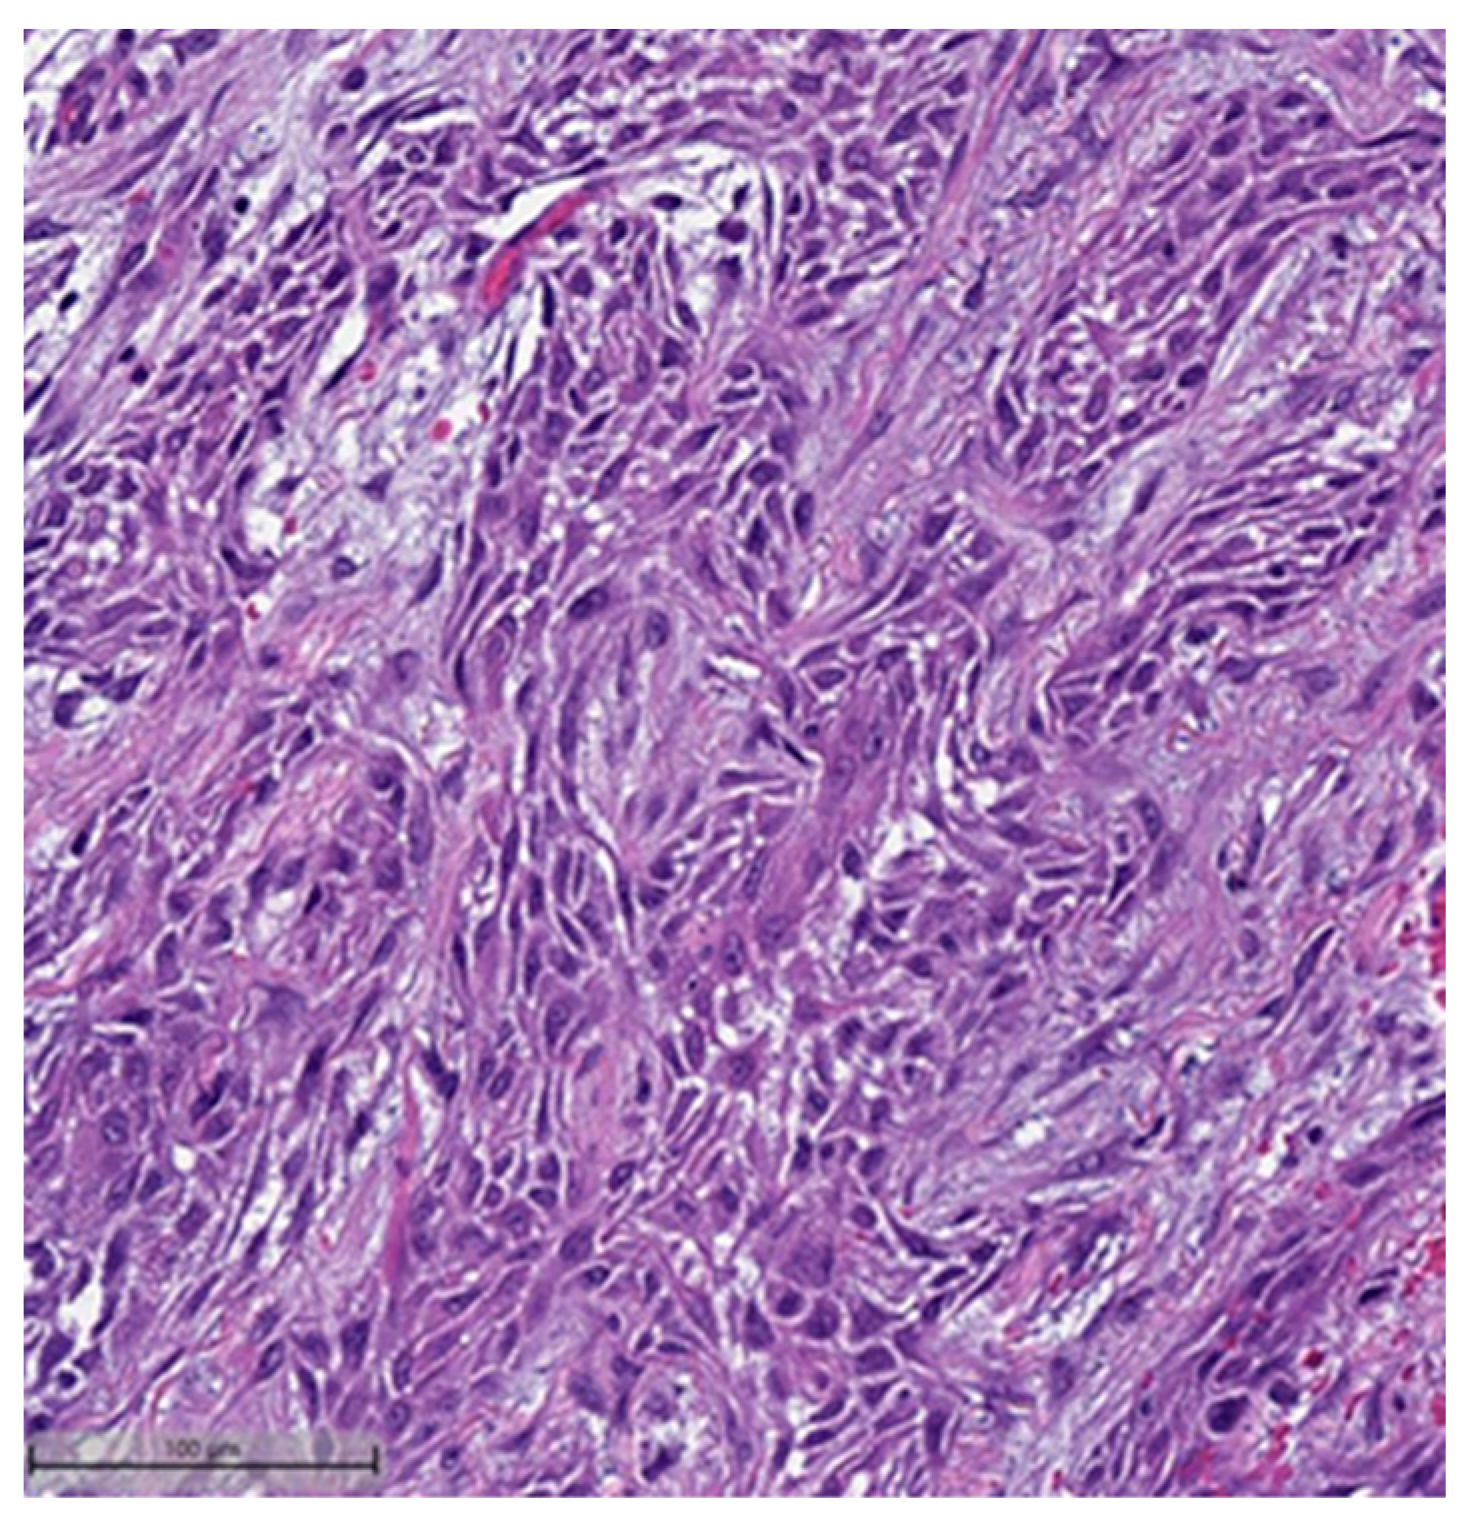

Figure 4.

Spindle cell carcinoma component with pleomorphic features (H&E, 20×).